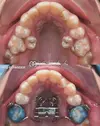

Diş Çapraşıklığı

Diş Çene ve Yüz Bölgesi Gelişim Yetersizlikleri